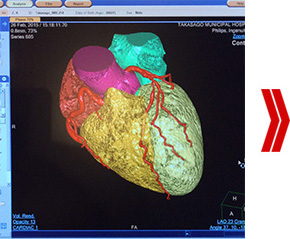

撮影された画像を再構成し、3D表示します。

具体的には、CTデータは平面画像であり、3D表示に構成しても設計図的には平面画像のままです。これをポリゴンと呼ばれる三角形の集合体で立体画像を構築変換していきます。このデータがSTLと呼ばれるデータ形式で、3Dプリンタを活用して造型モデルを作成するために必要なデータ形式になります。 よって、変換が正常に完了しないと3Dプリンタでの出力ができません。